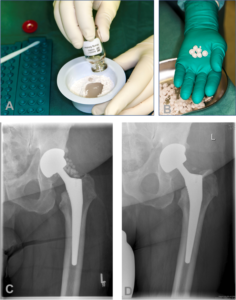

محمي: Knee Surgery جراحة الركبة